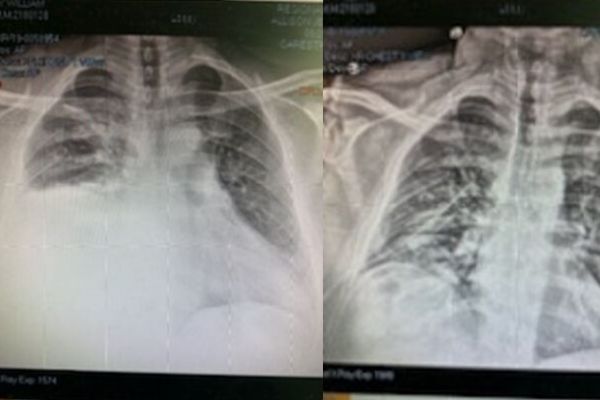

Now that I had a suction tube in my lungs, we have to watch the amount of blood being removed. We watch my "lung blood box", as I called it, and the x-rays to monitor my status. Tuesday afternoon a surgeon paid me a visit. He gave the hard truth. The suction is only going to remove so much. If we don't get enough blood out of my right lung I will have to have surgery to scrape it out.

Chest x-ray looks great surgeon said fluid looks to have gone out and change to water seal instead of suction—-surgeon said all his work is paying off and very pleased. Surgery not out of possibility until tube is out but he's super happy with where he's heading

The above was just after 9am. It was some amazing emotional news.